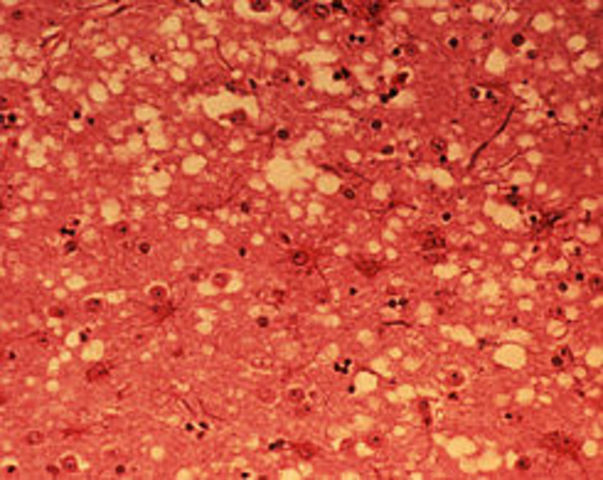

• Encefalopatía Espongiforme bovina “vacas locas”

Encefalopatía Espongiforme bovina “vacas locas”

La enfermedad de las vacas locas, o encefalopatía espongiforme bovina, es una enfermedad causada por priones, y que se puede transmitir a los seres humanos a través del consumo de partes de animales infectados, sobre todo tejidos nerviosos.